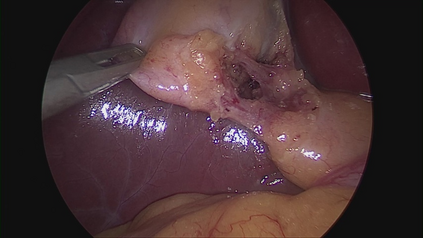

Large Vision-Language Models offer a new paradigm for AI-driven image understanding, enabling models to perform tasks without task-specific training. This flexibility holds particular promise across medicine, where expert-annotated data is scarce. Yet, VLMs' practical utility in intervention-focused domains--especially surgery, where decision-making is subjective and clinical scenarios are variable--remains uncertain. Here, we present a comprehensive analysis of 11 state-of-the-art VLMs across 17 key visual understanding tasks in surgical AI--from anatomy recognition to skill assessment--using 13 datasets spanning laparoscopic, robotic, and open procedures. In our experiments, VLMs demonstrate promising generalizability, at times outperforming supervised models when deployed outside their training setting. In-context learning, incorporating examples during testing, boosted performance up to three-fold, suggesting adaptability as a key strength. Still, tasks requiring spatial or temporal reasoning remained difficult. Beyond surgery, our findings offer insights into VLMs' potential for tackling complex and dynamic scenarios in clinical and broader real-world applications.